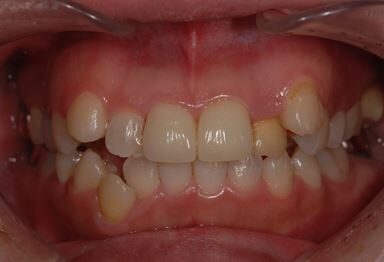

| 性別/年齢 | 女性 / 31歳 | ||||||||||||||||||||||||||||||||

| 治療方針 | セラミック治療により、審美的回復を行う。 | ||||||||||||||||||||||||||||||||

| 治療内容 | CAD/CAMオールセラミッククラウン1本(オールセラミック用土台1本)、オールセラミッククラウン2本(オールセラミック用土台2本) | ||||||||||||||||||||||||||||||||

| 総治療費 | 341,775円 | ||||||||||||||||||||||||||||||||

| 治療期間 | 10ヶ月 |